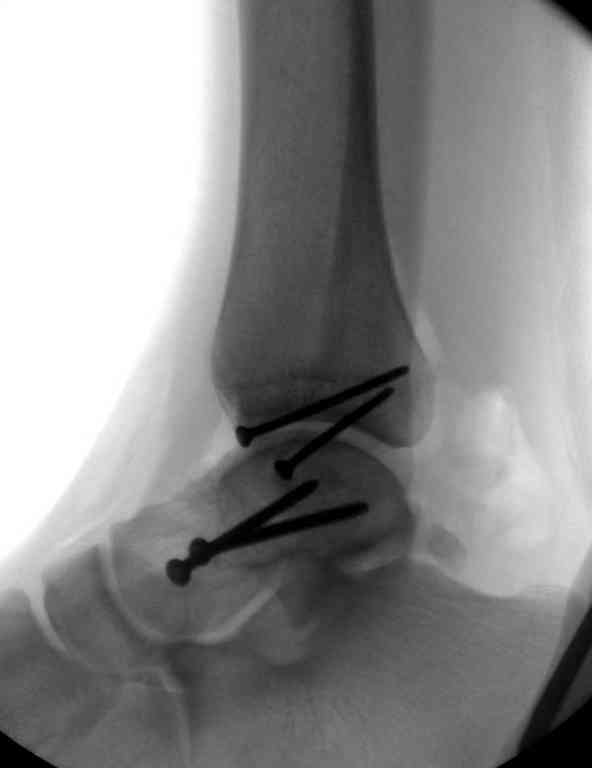

Переломовывих тарана с повреждением медиальной стороны. Через 4 часа после поступления проведена репозиция и фиксация тарана после Irrigation&Debridment. Частичное несращение медиальной лодыжки не беспокоит, вернулся к активному образу жизни. Полная нагрузка разрешена через 11 недель. Финальные снимки через 11 месяцев.

Из-за многооскольчатости дистальной части малоберцовой, где невозможно было провести фиксацию шурупами, перелом зафиксирован подпирающей пластиной, которая должна служить дополнением отсутствующей дистальной части малоберцовой (lateral cortex substitute).

Для стабильности два шурупа на синдесмоз.

Медиальную рану с приближенными краями продолжаем вакуумировать (KCI). Наружный фиксатор оставлен на пару недель, надеюсь, небольшая рана будет гранулировать и закроется без кожной пластики. Фиксация медиальной ложыжки не планируется.